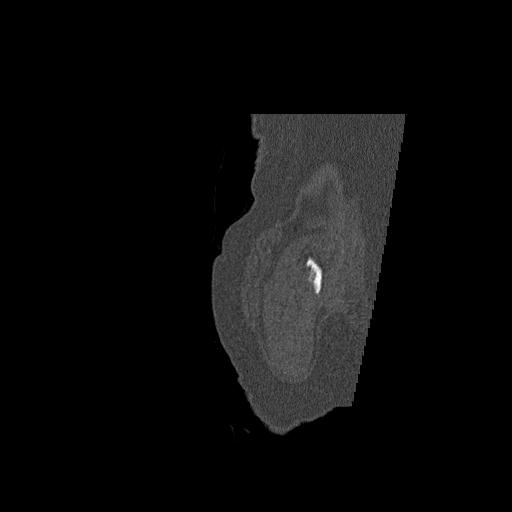

102755 1/4 2R 1/15 2R 右足関節 68歳女性 右三果脱臼骨折